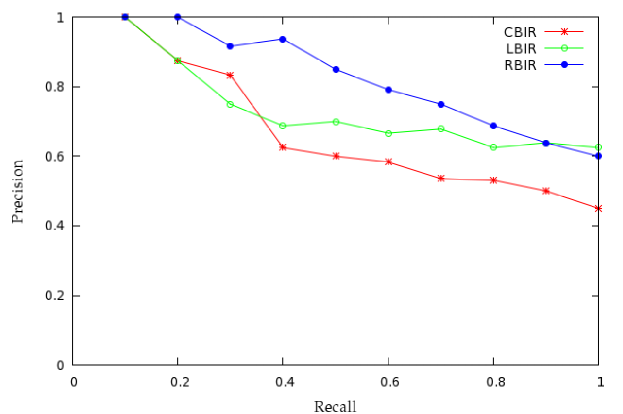

The two indexing and retrieval techniques implemented are: RBIR and LBIR. The retrieval performance is measured using precision and recall. We have experimented with a small database of 100 images of 4 classes, each of 25 images. These images are of 256 x 256 GIF format obtained from brain atlas of Harvard University. Each of the 100 images were used as query image and performance evaluated. Precision results are computed from the number of similar images (i.e., images belonging to the same class) in the top 10 retrieved images. Table 6, 7 and 8 shows results depicting the Precision rates for 4 different classes tabulated for retrieval from top 1 to top 10 retrieved images. The results for RBIR is shown to be better when compared to CBIR and LBIR, which leads to almost 10 percent increase in precision rates. Table 9 depicts the Recall rates for the same 4 different classes in the database. Here also, each of the 100 images were used as a query image and the number of matches in the top 20 retrieved images was counted and is shown to drastically increase recall rates by almost 10 percent. The precision recall graph for plotting the average precision retrieval rates for top 10 retrievals of the three indexing schemes is shown in Figure 3.

We have implemented two methods of indexing and retrieval namely: i) region-based indexing and retrieval and ii) location-based indexing and retrieval. Hash structure is used to index images. The retrieved images are sorted using Euclidean distance measure in the decreasing order of similarity against the query image. The performance of both the systems have been measured using standard precision versus recall graphs. Region-based indexing and retrieval gives significantly better results of 81.7 percent precision as compared to location-based indexing and retrieval which gives 72.74 percent precision. This is because, in most of the cases the tumor is located in the central position. The results are also compared with CBIR which gives 65.33 percent precision.